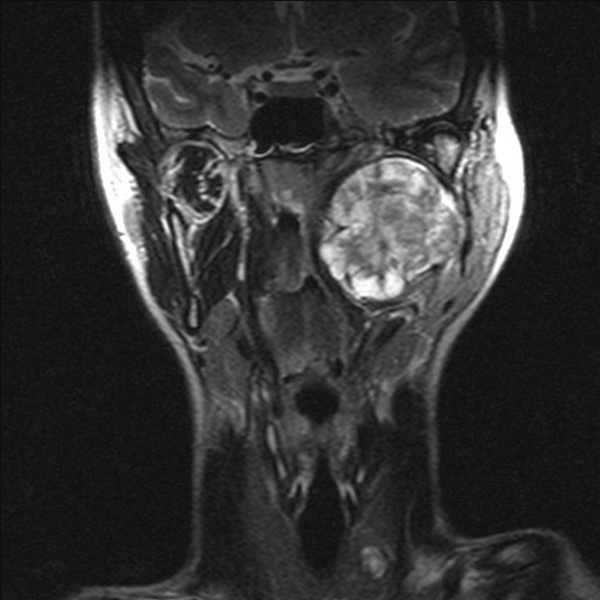

Parapharyngeal pleomorphic adenoma